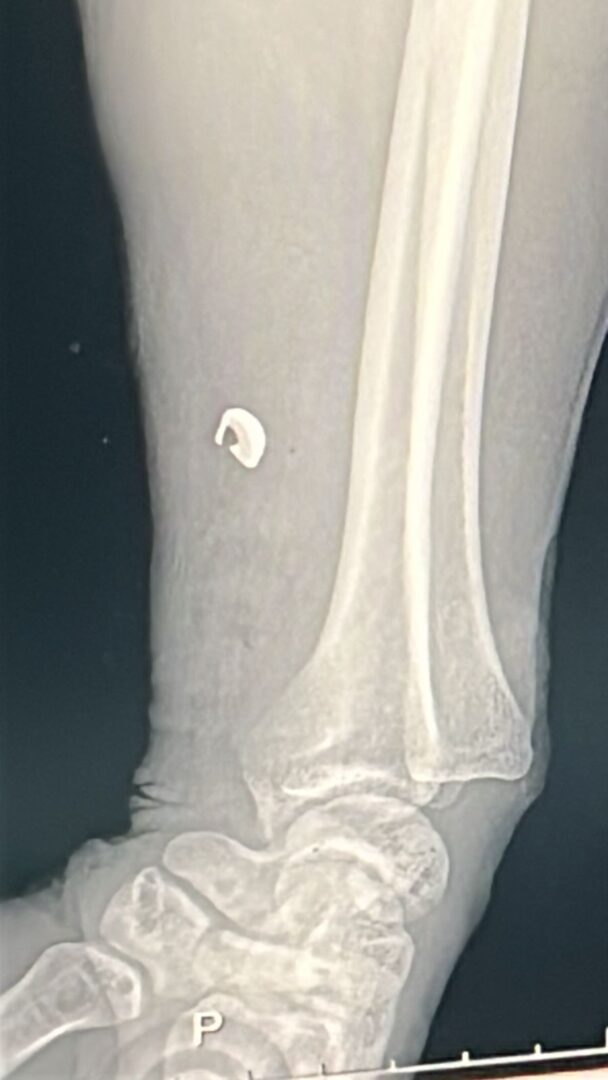

Tras los estudios médicos correspondientes, se confirmó que la lesión fue provocada por un proyectil de arma de fuego, quedando un fragmento incrustado en el antebrazo del lesionado. El calibre del proyectil no pudo ser determinado por el personal médico.